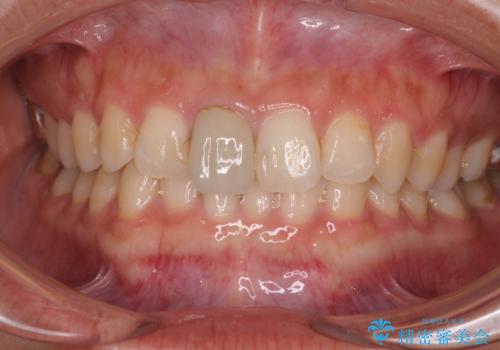

色、形ともに自然で嬉しいですと笑顔で言っていただけました。